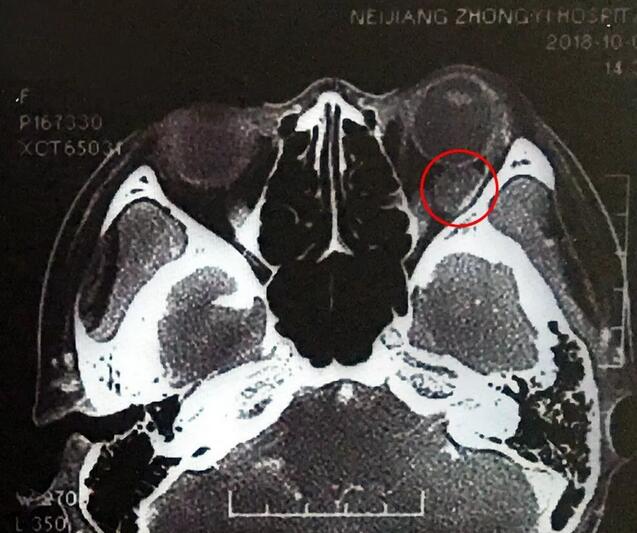

小何是四川南部县人,今年20岁,在内江上大学。今年9月底开始,出现头痛、反复呕吐,吐得连药都吃不下。医生建议小何做了脑部CT,“结果显示左眼眼球后部有个东西,经过进一步检查竟是肿瘤!”这对小何来讲真是个晴天霹雳。

在成都易游体育,经过详细检查,罗清礼教授根据他40余年的丰富经验,判断为淋巴血管瘤。“现在,虽然她双眼的视力都是1.0,但是眼内肿瘤已经接近眼球那么大了,若不及时手术必将失明。”

罗教授介绍,淋巴血管瘤早期症状并不明显,“一般人感冒是不会头痛、呕吐的。小何的感冒非常幸运,她感冒后引起淋巴增生,导致肿瘤内出血,然后引起了头痛、呕吐等症状,让她能够尽早发现了肿瘤。”患者的肿瘤体积较大,位置较深,位于眶间且紧挨着视神经,手术稍有差错,就可能导致患者视力丧失、大出血等情况发生。得知手术风险后,患者和家属表示非常理解并信任罗教授,坚决要求手术医治。